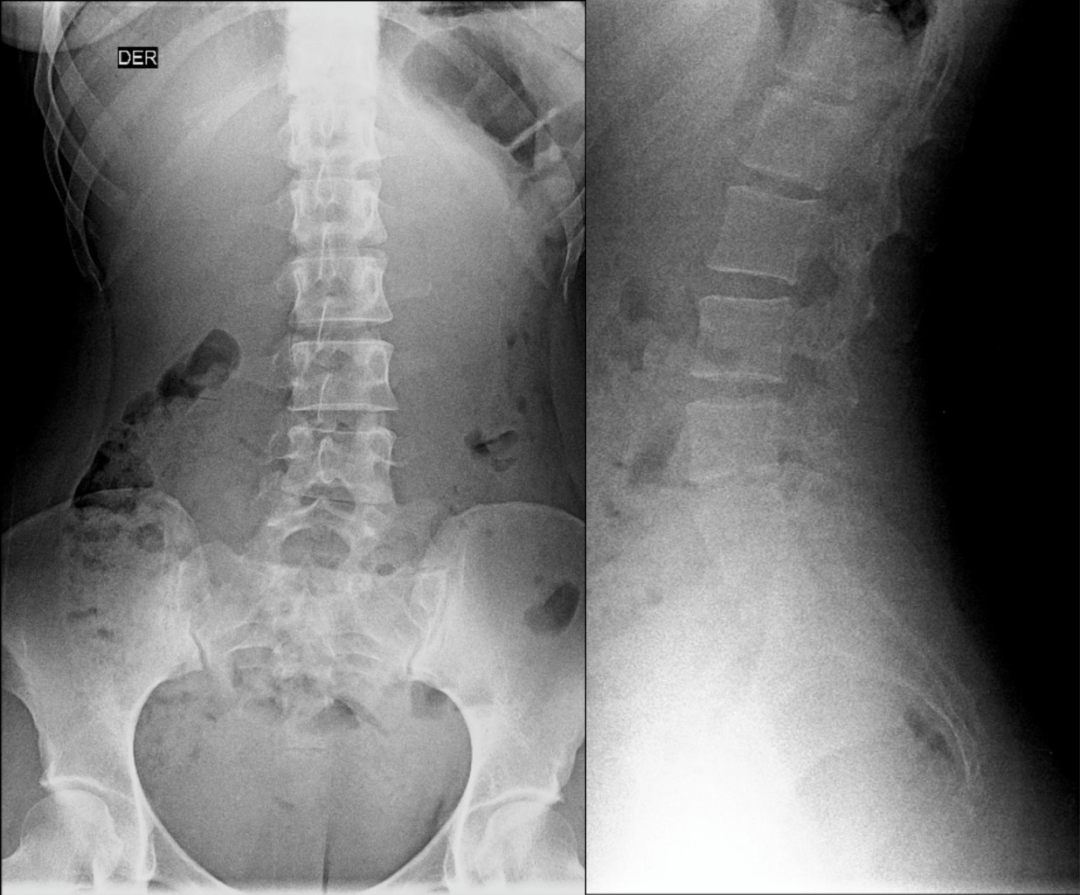

腰椎骶化及骶椎腰化均是椎骨发育的异常,腰椎骶化是指第五腰椎外型类似骶椎形态,并构成骶骨块的一部分,一侧或两侧横突肥大呈翼状,与骶骨发生融合或形成假关节。骶椎腰化是指第一骶椎演变成腰椎样形态,即第一骶骨从筋骨块中游离出来形成第6个腰椎。

这是一个最关键和准确的鉴定方法,国内著名骨放射学家杨世埙教授指导过,只要大家留意关注腰椎横突"三长/四翘/五宽",L3横突是最长的,L4横突是上翘的,L5横突最宽,特别用在胸椎腰化合并L5骶化的时候比较实用。

1984年,Castellvi 提出LSTV分类系统将移行椎分为Ⅰ-Ⅳ型。

Ia型(单侧)和Ib型(双侧):横突肥大宽度超过19mm

IIa型(单侧)和IIb型(双侧):横突与骶骨相接触形成假关节

IIIa型(单侧)和IIIb型(双侧),横突与骶骨发生骨性融合

IV型:一侧横突与骶骨形成假关节,另一侧形成骨性融合

目前,腰骶移行椎以 Castellvi 的分类方法最为常用。其主要根据横突形态及其与骶骨、髂骨是否融合或形成假关节而分为 4 型,Ⅰ、Ⅱ、Ⅲ型又根据单、双侧分为A、B两个亚型。

正常I型:主要为腰5横突发育不良,横突宽度大于19mm,并将其分为两个亚型Ia(单侧横突发育不良)或Ib(双侧横突发育不良)

L5 右侧横突肥大,为 Ⅰa 型

L5 双侧横突肥大,为Ⅰb 型

II型:表现为不完全的腰椎骶化,具有增宽的横突,并且和骶骨形成假关节,并将其分为两个亚型IIa(单侧关节形成)或IIb(双侧关节形成)

L5 左侧横突肥大,假关节形成,为 Ⅱa 型

L5 双侧横突肥大,假关节形成,为 Ⅱb 型

III型:单侧(IIIa)或双侧(IIIb)腰椎完全骶化,腰5横突与骶骨完全骨性融合

L5 右侧横突肥大与骶骨发生骨性融合,为 Ⅲa 型

L5 双侧横突与骶骨骨性融合,为 Ⅲb 型IV型:一侧为II型即腰5横突与骶骨形成假关节,对侧为III型即腰5横突与骶骨形成骨性融合

IV 型即混合型:L5 双侧横突肥大,一侧与骶骨相接触为Ⅱ型表现,另一侧与骶骨形成骨性融合为Ⅲ型移行椎一般不引起症状,但是这种畸形可影响脊柱的稳定并逐渐产生症状,移行椎较正常椎体潜在着更多不稳。由于负重及运动不平衡,而引起腰痛。

它与腰骶部疼痛存在密切的相关性是不可忽视的, 并干扰诊断与之症状相近的其它疾病, 如椎间盘突出、致密性骨炎、强直性脊柱炎等等, 当然这其中有些疾病可以并存, X 线、CT 检查在腰骶部移行椎的诊断中有重要意义, 不仅能对本病做出诊断, 并且有助于鉴别诊断。